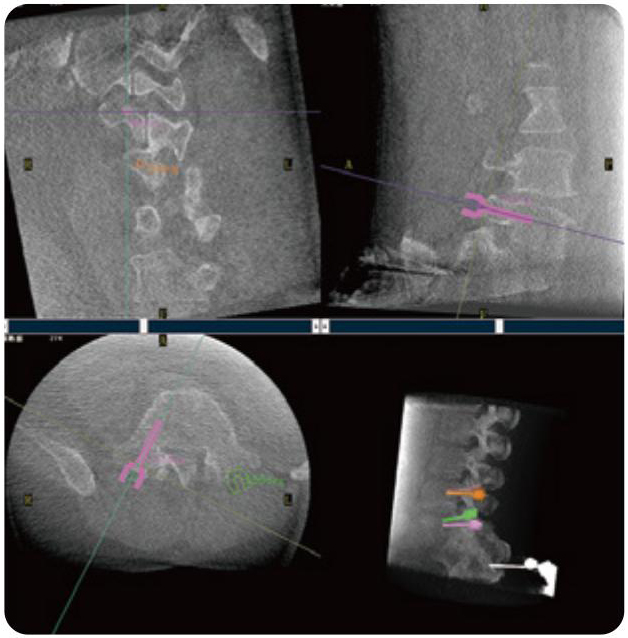

PL300B可應(yīng)用于多節(jié)段脊柱外科手術(shù),輔助醫(yī)生定位病灶部位,為脊柱外科手術(shù)(經(jīng)皮椎體成形術(shù)、椎弓根螺釘內(nèi)固定術(shù)等術(shù)式)提供術(shù)前手術(shù)流程規(guī)劃、入釘位置、角度可視化引導(dǎo),模擬仿真入釘輔助。

PL300B搭配普愛(ài)醫(yī)療自主研發(fā)生產(chǎn)的平板3D C形臂,借助一體化自適應(yīng)配準(zhǔn)( 軌跡配準(zhǔn))技術(shù),通過(guò)追蹤C(jī)形臂三維采集軌跡,自動(dòng)完成圖像坐標(biāo)建立和系統(tǒng)坐標(biāo)配準(zhǔn)。配準(zhǔn)精度更高,操作步驟少,系統(tǒng)運(yùn)作效率高。